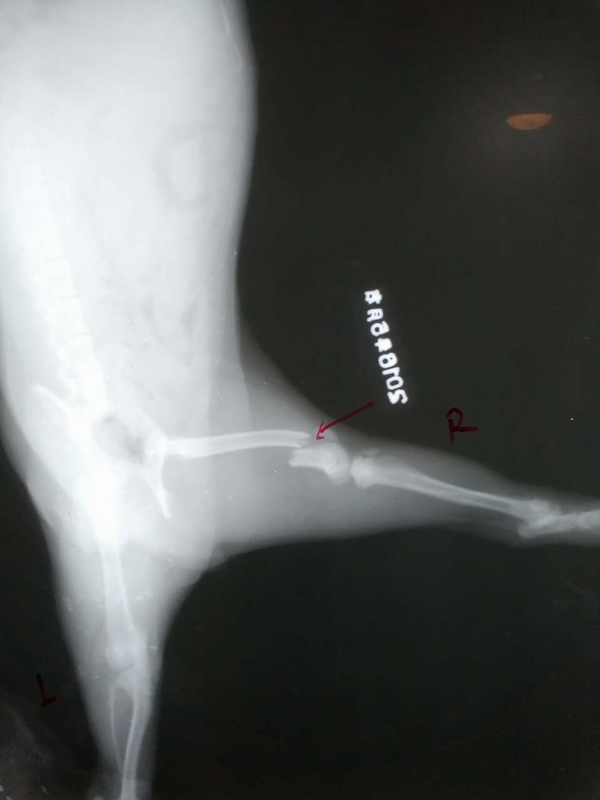

后肢股骨遠端骨折整復手術